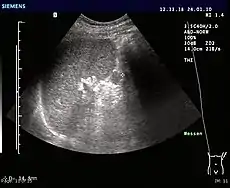

Ultrasonography of an accessory spleen.

If splenectomy is performed for conditions in which blood cells are sequestered in the spleen, failure to remove accessory spleens may result in the failure of the condition to resolve.[1] During medical imaging, accessory spleens may be confused for enlarged lymph nodes or neoplastic growth in the tail of the pancreas,[5] gastrointestinal tract, adrenal glands or gonads.[2]